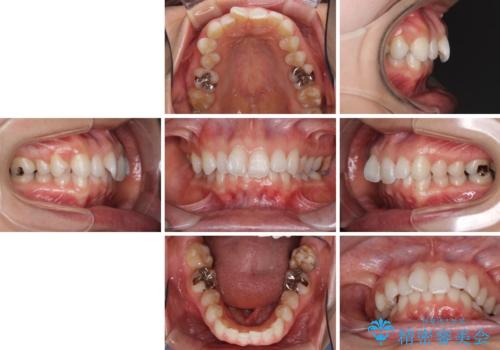

- 奥歯の虫歯と前歯のデコボコや突出感を気にして来院された患者様です。

上顎歯列が、下顎に対して前方にありましたが、口元に出っ歯の印象がなかったため、親知らずを抜歯した上で、上顎歯列全体を後方に移動させることとしました。

咬合力が強いため、アンカースクリューを使用し、ワイヤー装置にて矯正治療を行うこととしました。

矯正治療後は、奥歯の虫歯や銀歯を補綴・修復治療することとしました。

上顎歯列を下顎に対して4mmほど移動させる必要があったため、治療は長期化することが予想されましたが、患者様にはこちらの期待以上にゴムかけなどに協力いただき、補綴治療も含めて2年強で終えることができました。